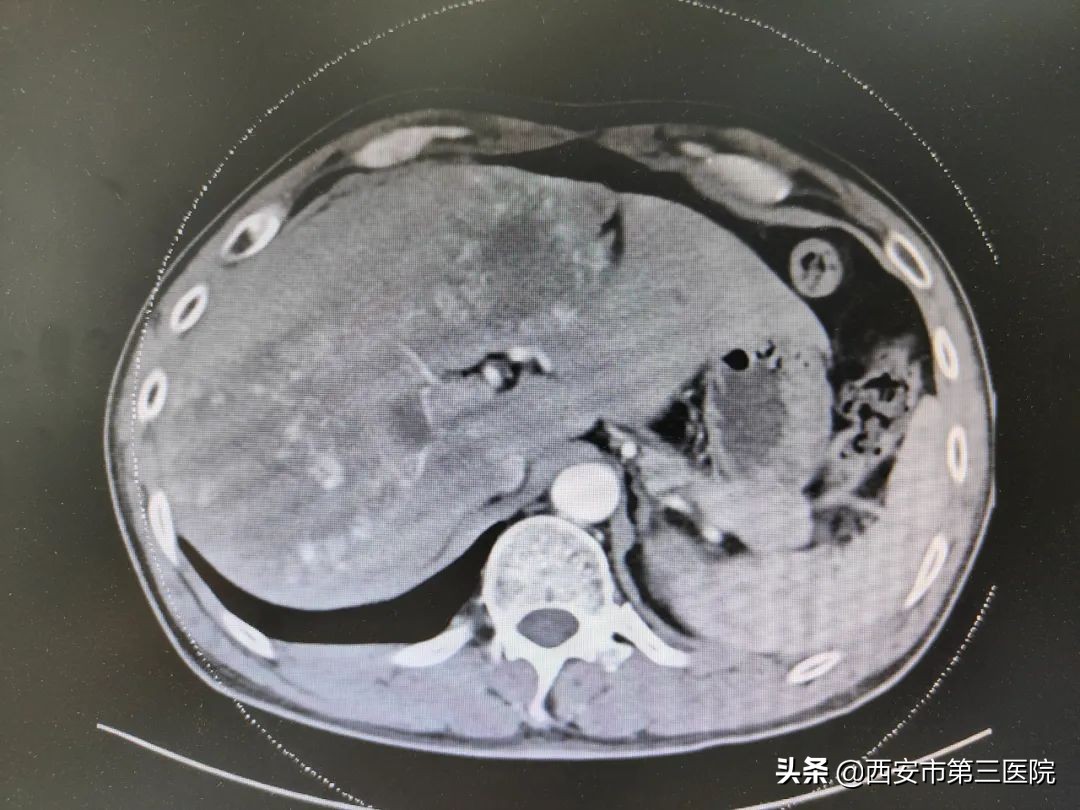

患者中年男性,腹部超声和腹部CT均显示肝内多发血管瘤(13处,最大处为6.3*12cm)。DSA示:腹腔干发出肝总、脾动脉、胃左动脉,肝总动脉发出肝左、右动脉,肝左、右动脉明显增粗,实质期肝左、右叶可见多发点、片状血管湖,呈弥漫性分布。静脉期门静脉主干显影尚可。将RH导管头端置于肝总动脉,再将微导管超选至肝左、右动脉血管瘤供血动脉,再将平阳霉素16mg与碘油15ml充分混匀后行瘤供血动脉栓塞。栓塞后行DSA示:肝内血管湖染色基本消失。患者未诉特殊不适,术毕拔除导管及鞘管,穿刺点加压包扎,安返病房。